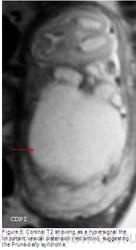

Рисунок 1: